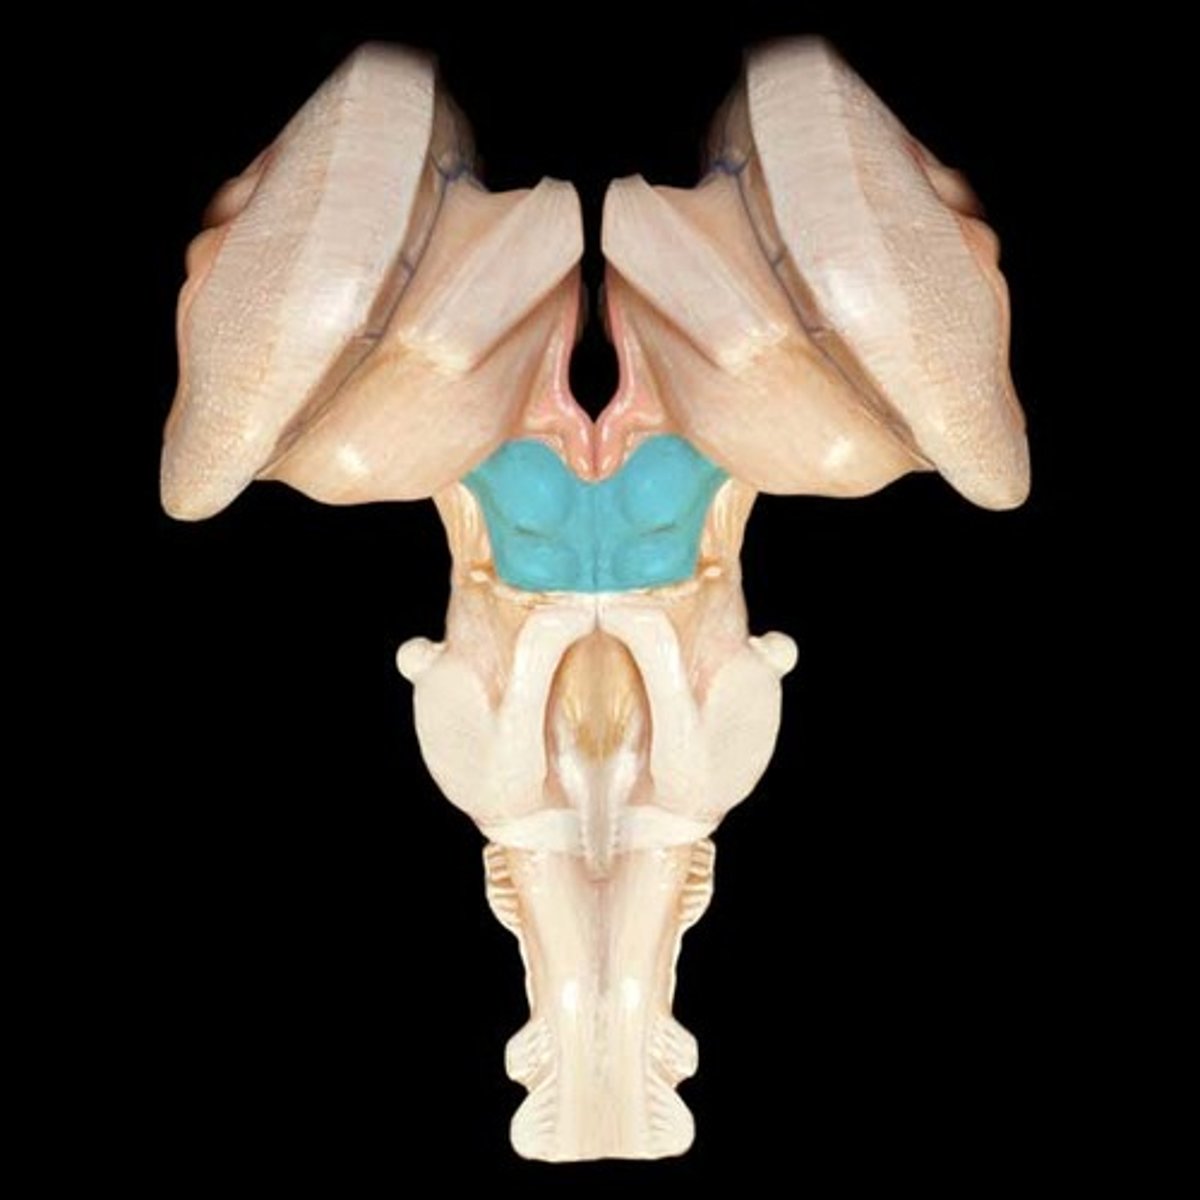

superior cerebellar peduncles

middle cerebellar peduncles

pons

medulla oblongata

pyramids

inferior cerebellar peduncles

cerebellum

right and left cerebellar hemispheres

vermis

fourth ventricle